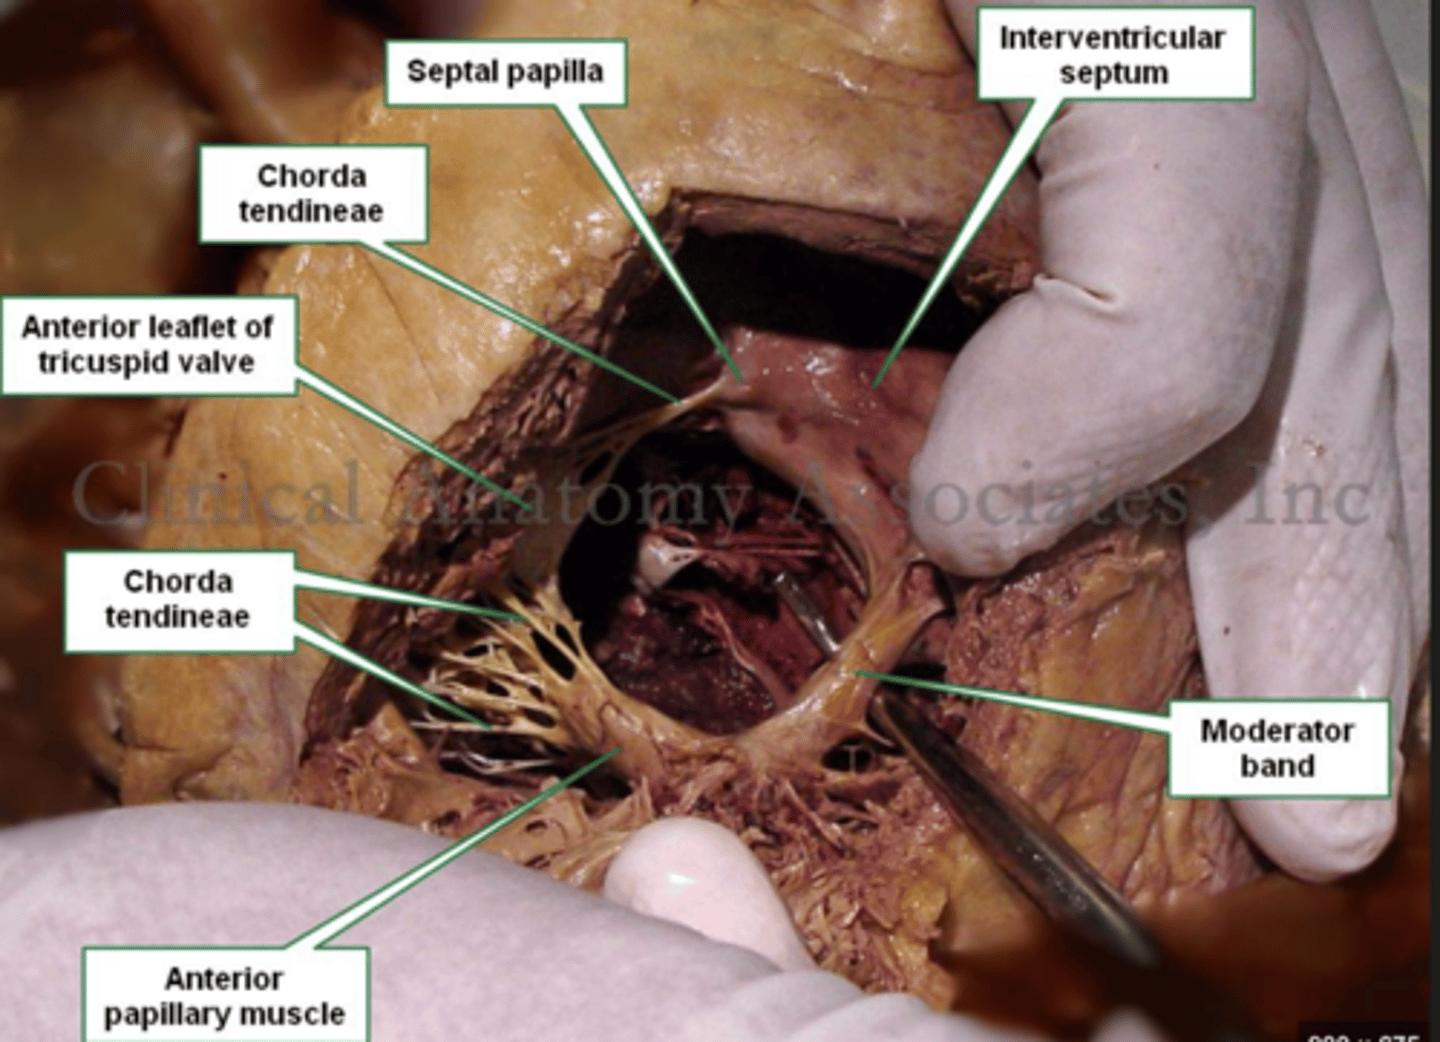

What are the 3 cusps of the tricuspid valve?

Anterior

Posterior

Septal

What connect the cusps of the valve a to papillary muscles in the

right ventricle?

Chordae tendinae

With the contraction of the walls of the ventricle what's the action of the papillary muscles?

contract as well

With the contraction of papillary muscles what will be happen with the valve?

Close

What is the septomarginal trabeculae (or moderator band)?

Part of the conduction system of the heart.

electrical waves pass through this band to reach the papillary muscles.

What role do the papillary muscles and chordae tendineae play in the function of the tricuspid valve?

During ventricular systole (contraction), the tricuspid valve closes

The papillary muscles contract at the same time as the ventricle.

This contraction tightens the chordae tendineae, pulling the valve leaflets taut and holding them in place.

This mechanism prevents the valve leaflets from prolapsing (bulging back) into the atrium under the high pressure of ventricular contraction.

What role does the moderator band play in the conduction system?

Allows the wave to reach the papillary muscles, inducing their contraction simultaneously with that of the ventricles.

REMEMBER: PAPILLARY MUSCLES ACT THROUGH THE CHORDAE TENDINAE TO CONTROL THE TRICUSPID AND MITRAL VALVES.